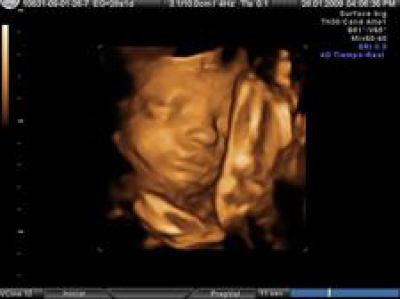

Y me ha sorprendido por lo que tendría que ser pero no es. Porque precisamente en nuestra época, en nuestra nación y en contra de nuestra cultura, se están llevando a cabo masacres mucho más numerosas, ejecuciones masivas, terriblemente violentas, de criaturas indefensas antes de su nacimiento. Una media anual de cien mil sacrificios de niños, victimados mediante los nuevos ritos más sofisticados y metódicos que los ancestrales, y realizados por enriquecidos chamanes. Millones de vidas que comenzaban aniquiladas por fármacos específicos, sueros salinos hipertónicos, descuartizamientos y aspiración. Restos de niños que las investigaciones arqueológicas futuras, jamás encontrarán, porque no se les concedió el derecho a ser dignamente enterrados, ni ser envueltos en simples mortajas. Simplemente fueron considerados como desechos hospitalarios para ser triturados antes de eliminarlos a la basura o ser incinerados. El sacrificio masivo actual de vidas infantiles no son la necesidad de una comunicación sobrenatural, la exigencia de una petición o agradecimiento a los dioses. Estos dioses sobrenaturales han sido sustituidos en la inmensa mayoría de los casos por los dioses personales actuales del egoísmo, la comodidad, la amoralidad, la banalización o la cobardía por el que las propias madres sacrifican la vida de sus hijos, al considerarlos no un bien preciado sino un estorbo en su papel perversamente aleccionado de mujer libre.